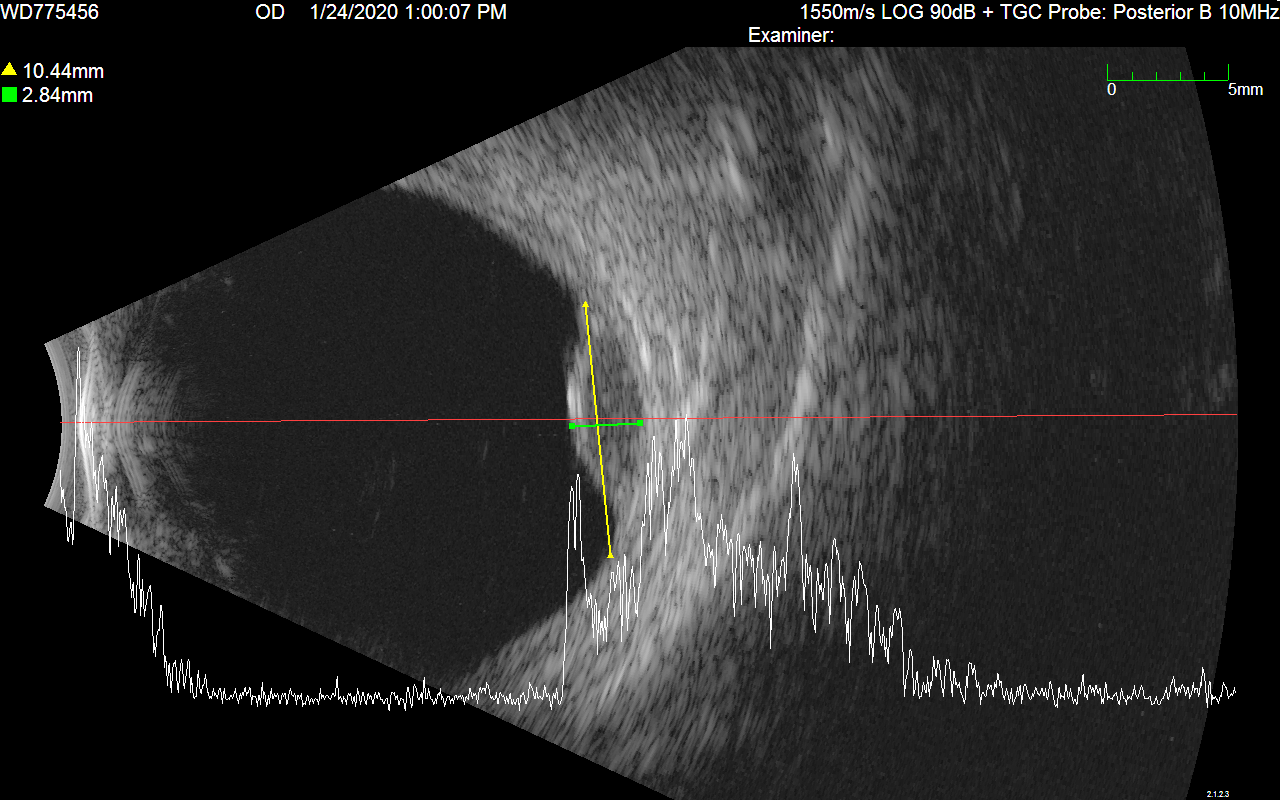

Ultrasound Images

A pair of ultrasound b-scans are used to determine the elevation of the tumor. Ideally, these images should illustrate cross-sections of the longest dimension of the tumor, and a plane perpendicular to that longest dimension. Radial and circumferential cross-sections are also acceptable. Eye tumors are often not clearly visible in CT (or MR) imaging alone. Ultrasound b-scans provided the most accurate measurements and cross-sections of ocular tumors for treatment planning purposes.

US1

US2